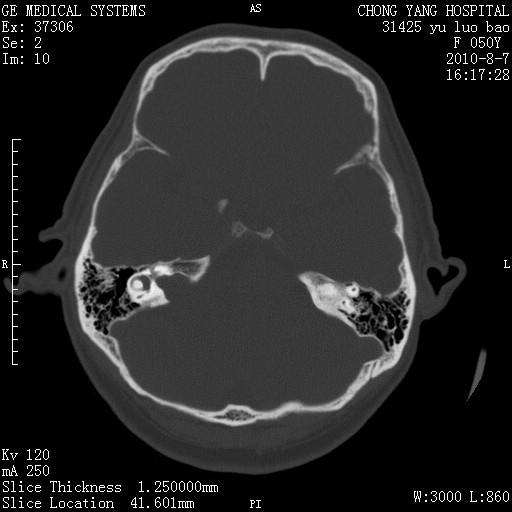

骨窗示右侧内听道扩大,考虑右侧听神经瘤。

右侧桥小脑角去等密度占位,右侧内听道扩大、骨质吸收,考虑:右侧听神经瘤,建议增强检查。

右侧内听道扩大、骨质吸收,中脑受压左移,考虑:右侧听神经瘤,建议增强检查。支持!